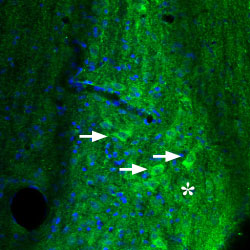

Expression of Adenosine A2A Receptor in mouse diagonal bandImmunohistochemical staining of mouse diagonal band using Anti-Adenosine A2A Receptor Antibody (#AAR-002). A2aR (green) appears in the broca of individual neurons (arrows) and in neuropil (asterisk). DAPI is used as the counterstain.

Expression of Adenosine A2A Receptor in mouse diagonal bandImmunohistochemical staining of mouse diagonal band using Anti-Adenosine A2A Receptor Antibody (#AAR-002). A2aR (green) appears in the broca of individual neurons (arrows) and in neuropil (asterisk). DAPI is used as the counterstain. Expression of Adenosine A2A Receptor in rat lungImmunohistochemical staining of paraffin emedded rat lung sections using Anti-Adenosine A2A Receptor Antibody (#AAR-002), (1:50). A2aR is expressed in the respiratory epithelium of the bronchioli (Br). Note that smooth muscle and endothelium in blood vessels are negative. Hematoxilin is used as the counterstain.